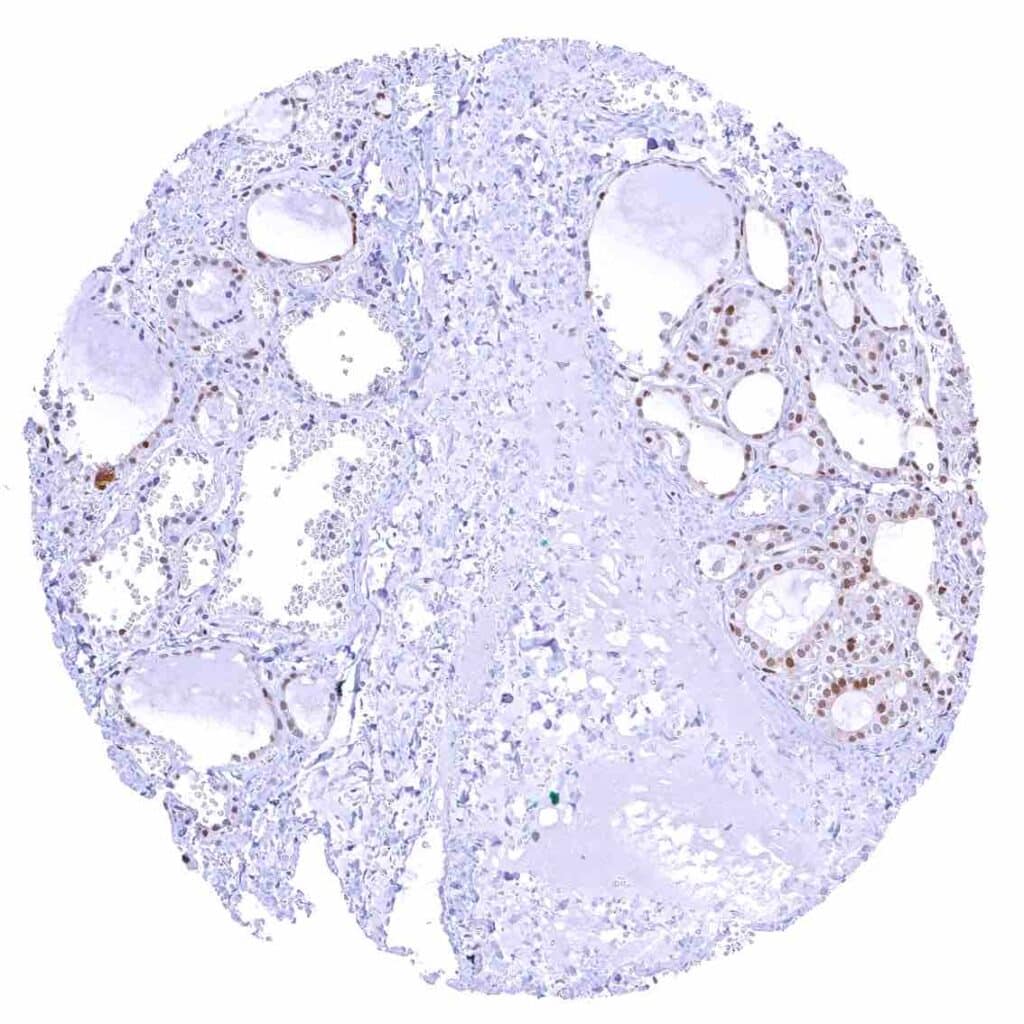

Thyroid gland – Weak to moderate nuclear p27 positivity of most follicular cells. .jpeg